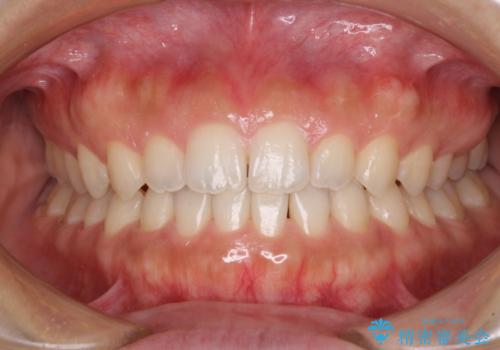

気になる隙間の再矯正 前歯をインビザライン・ライトで改善

- 後戻りによる上下前歯の隙間を気にして来院された患者様です。

歯列不正はそれほど大きくなかったため、インビザライン・ライトを用いて矯正治療を行うこととしました。

無理のないペースで治療を進め、9ヶ月で終えることができました。